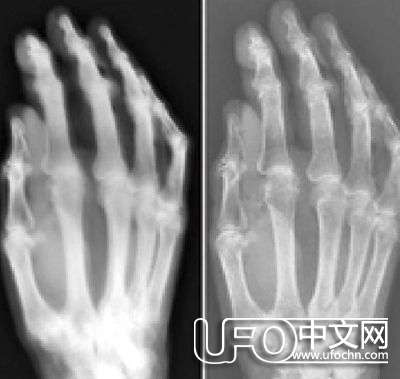

1 8 9 5年伦琴发现了X 射线,这一发现对这些想象起到了促进作用。人们很快就发现X 射线是无线电光谱另一端的不可见辐射,它的波长比光的波长短很多。令人吃惊的是,虽然X 光是不可见的,但是它能使不可见的事物可见,比如我们皮肤下的骨骼,这让人产生了恐怖的死亡预感。1 9世纪9 0年代,人们聚集在柏林乌兰尼亚天文台和纽约的托马斯· 爱迪生展示台,观看他们的骨骼出现在发光的X 光透视屏幕上。X光图像就像是“精神图像”的直接扩展,在1 9世纪七八十年代迅速流行,有人声称要通过无意间的二次曝光揭露鬼魂的真面目。还有一些人声称在照片中发现了新型隐形射线存在的证据,甚至认为照片中可以显示出思想的形状及灵魂。